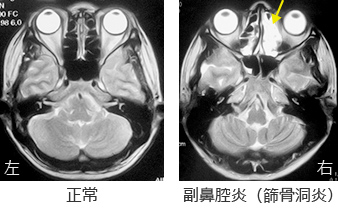

上のMRIが正常の患者さんで、右側が副鼻腔炎をおこした患者さんのMRIになります。目と目の間の部分が正常であれば黒い小さな部屋がいくつも見えるわけですが、副鼻腔炎では黄色い矢印で示しましたように、炎症をおこして全体的に白っぽく映っています。それが副鼻腔炎といわれるものです。症状としては、皆さんも経験されたように鼻づまり・色のついた粘りっ気のある鼻水がでたり、顔面が紅潮したり、痛くなったり、発熱したりします。